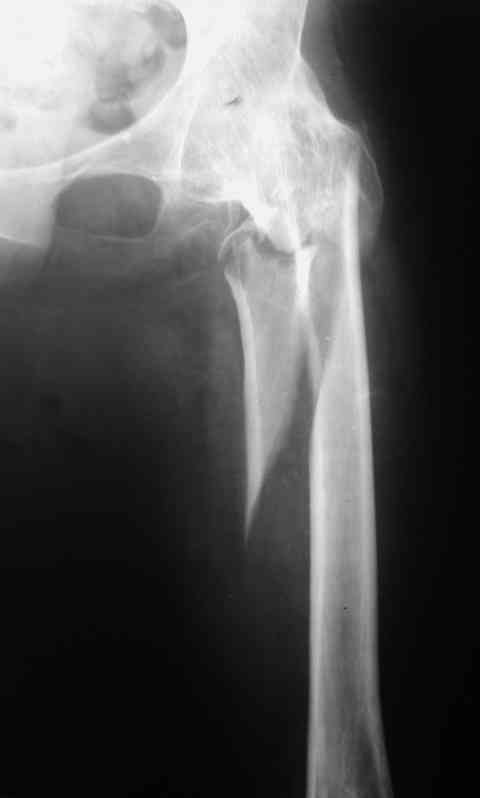

Рентгенограммы до и после. Больной профессор на кафедре сопромата и после детального изучения

особенностей имплантата, собственных рентгенограмм дал добро на операцию. Ваш вариант лечения вполне симпатичен.

Месяцев 6 назад оперировали такого больного (анкилоз после туберкулезного коксита 40 ле назад) интрамедуллярным стержнем PFNa. Ушел на своих ногах (с тростью кончно, как и до травмы). Больше не появлялся.